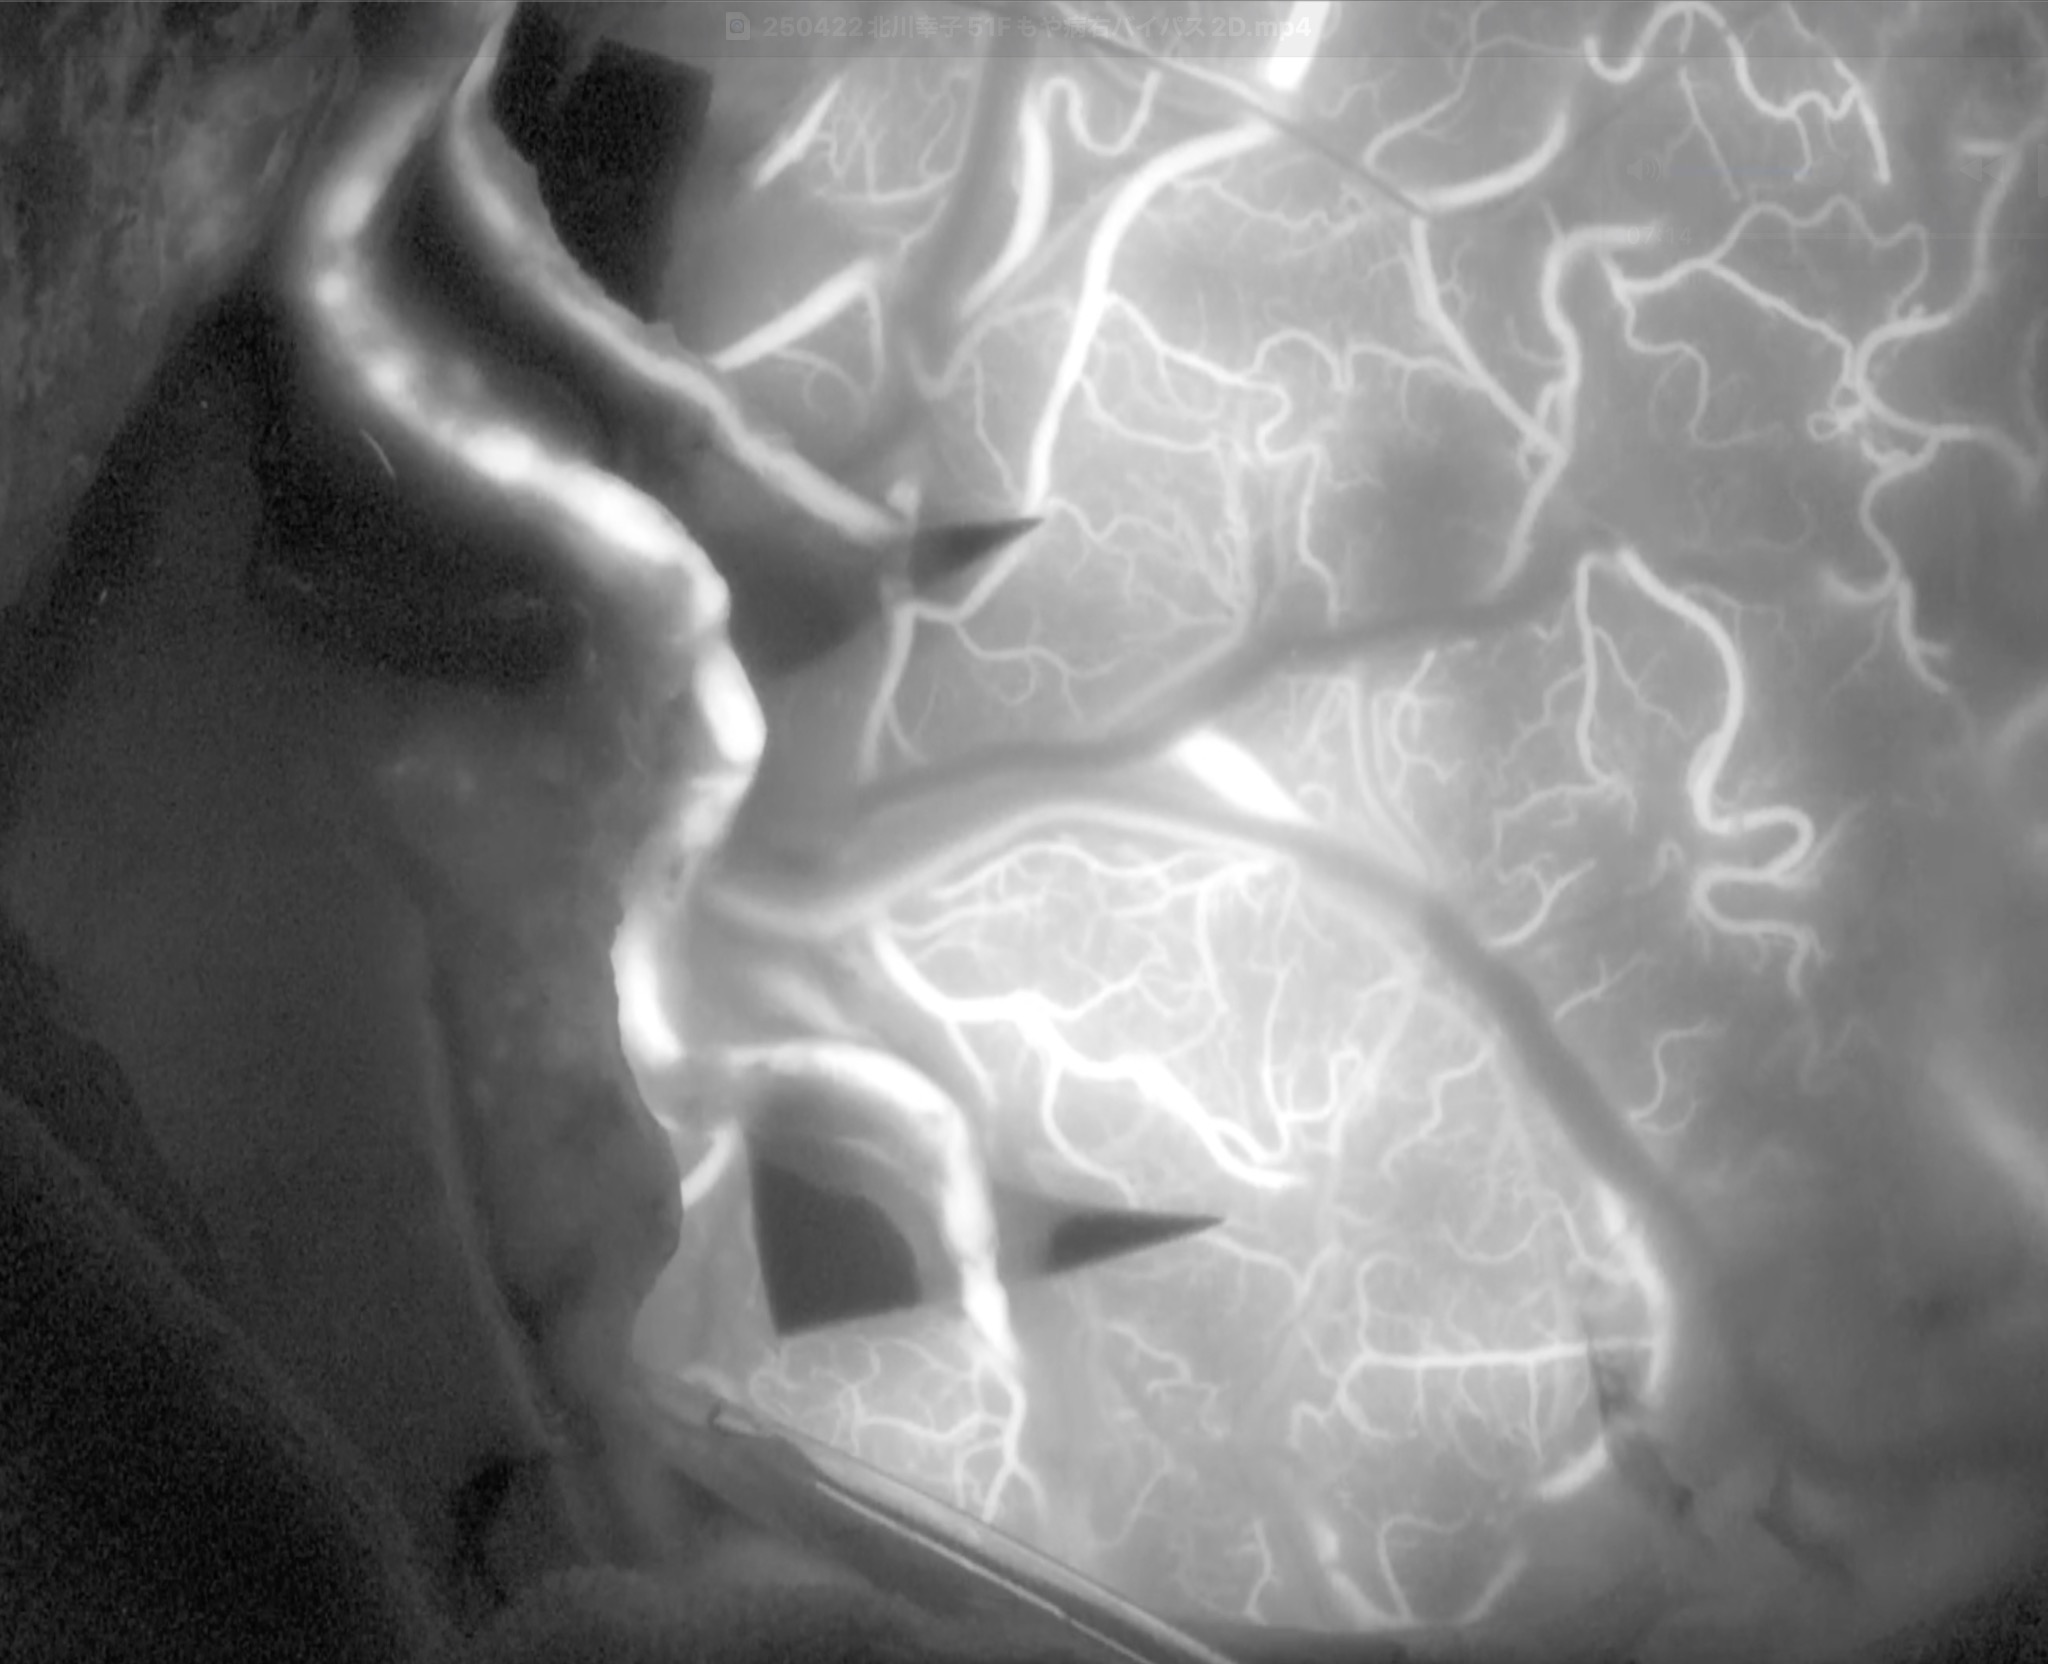

51歳女性の脳梗塞と脳室内出血を続けて起こした左片側もやもや病の患者さんをバイパス手術しました。STAがgaleaから外に出てGaleaの外に枝を出していたため皮弁翻展時にSTA頭頂枝が切れてしまい、端端吻合をしてからバイパスに用いました。2本とも無事開通しました。脳血流が著明に低下していたので術後の過灌流が心配で厳重な術後血圧管理を行いましたが、幸い順調な回復を見せています。

51歳女性の脳梗塞と脳室内出血を続けて起こした左片側もやもや病の患者さんをバイパス手術しました。STAがgaleaから外に出てGaleaの外に枝を出していたため皮弁翻展時にSTA頭頂枝が切れてしまい、端端吻合をしてからバイパスに用いました。2本とも無事開通しました。脳血流が著明に低下していたので術後の過灌流が心配で厳重な術後血圧管理を行いましたが、幸い順調な回復を見せています。